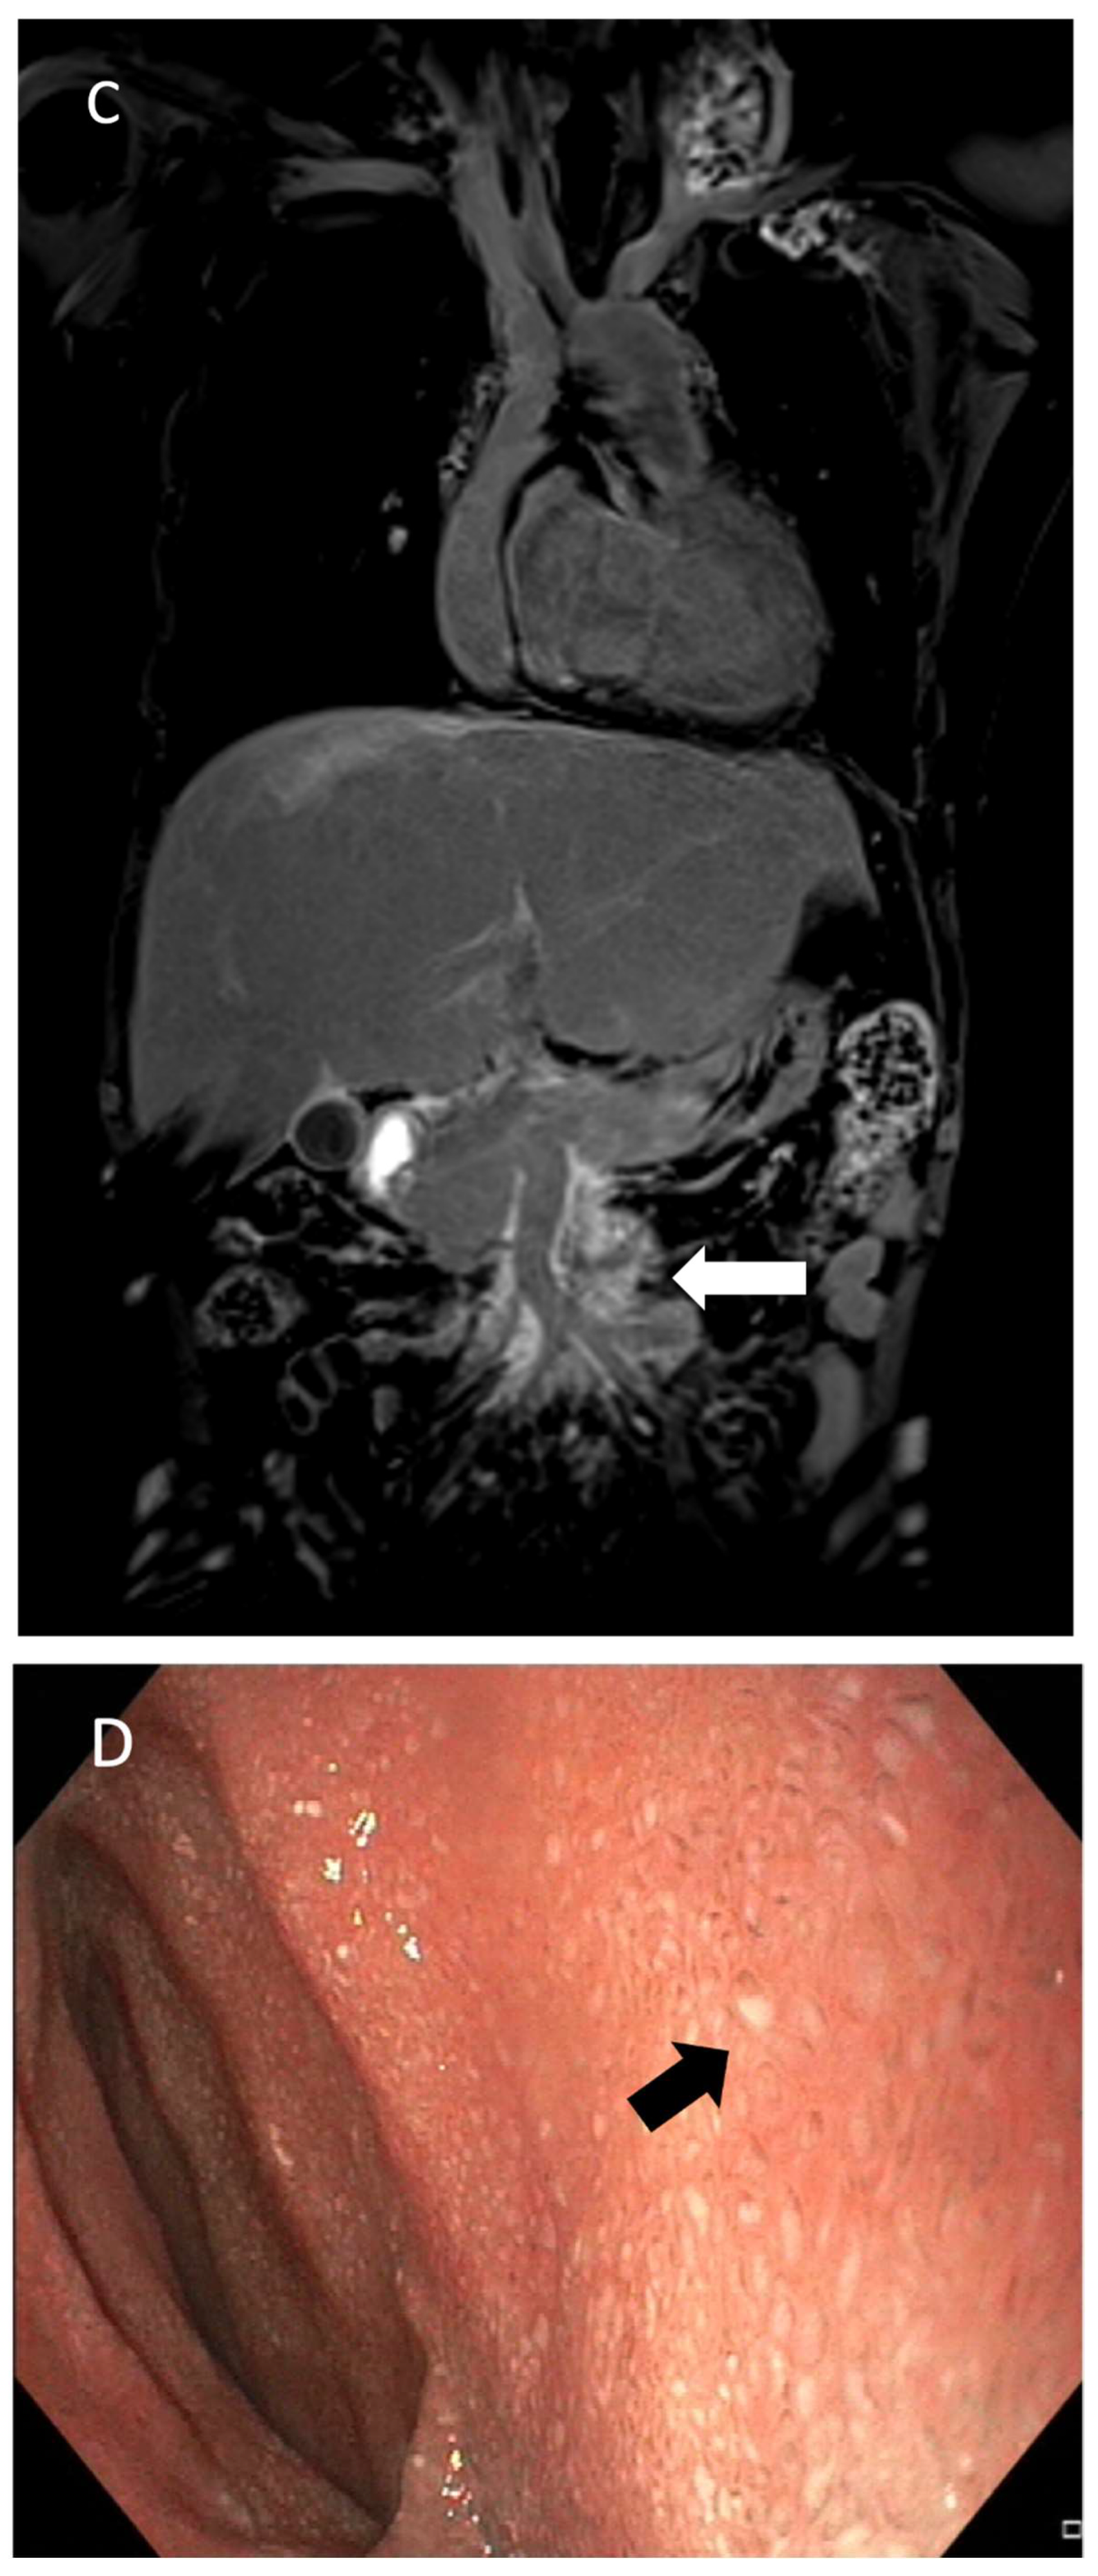

The most common abnormal imaging finding in patients with PLE is duodenal wall enhancement with leakage of contrast into the duodenal lumen [29,76] (Figure 11). This reflects the pathophysiology of abnormal flow patterns through the hepaticoduodenal lymphatic connection as a result of increased central venous pressure, absent thoracic duct, or abnormal lymphogenesis. This also corresponds to the endoscopic findings of “snowflake” appearance, representing dilated mucosal and submucosal lymphatic vessels, which are prone to rupture and leakage [77].

Other abnormal imaging features include chylous ascites, mesenteric lymphatic edema, retrograde mesenteric lymphatic flow, and retrograde flow into the peripancreatic lymphatic network. It is not uncommon to observe other associated abnormalities in the central conducting lymphatic system, including absence or dysplasia of the thoracic duct, abnormal lymphatic collateralization away from the midline, and chylous effusions [29,76].

Figure 11. A 21-year-old girl with a history of hypoplastic left heart syndrome and Fontan’s operation. (A) Conventional fluorosocpic intrahepatic lymphangiogram demonstrated abnormal hepatico-duodenal connections and dilated lymphatic channels (black arrow) along the duodenal wall. (B) Minimum-intensity-projection (MIP) coronal image of post-contrast T1-weighed intrahepatic DCMRL showed contrast leakage into duodenal lumen (white arrowheads). (C) Coronal image of post-contrast T1-weighed intrahepatic DCMRL showed abnormal enhancement of mesenteric lymphatics (white arrow), indicating retrograde mesenteric flow. (D) Endoscopic photo at second part of duodenum showed multiple tiny mucosal white specks (black arrow), compatible with snowflake appearance of lymphangectasia.